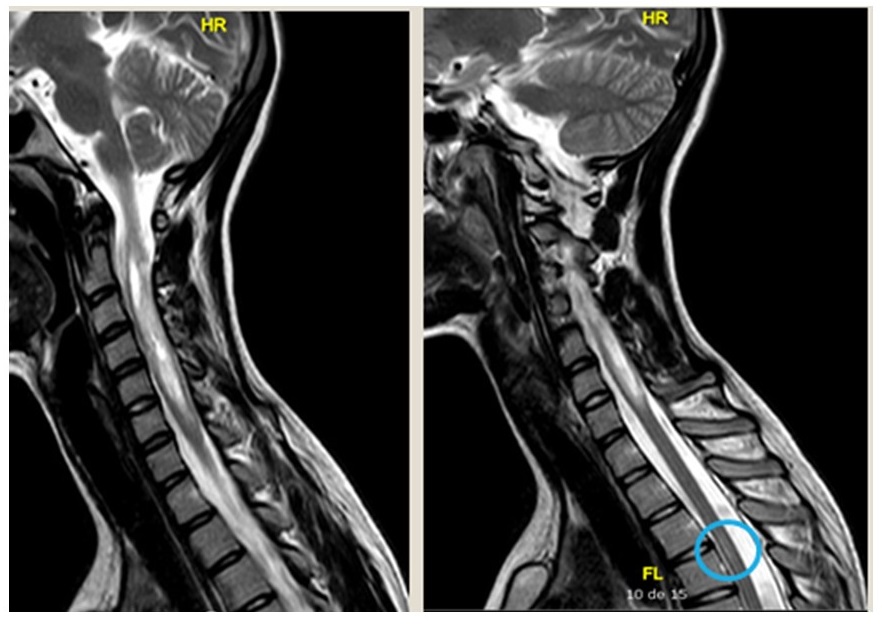

Se realiza analítica sanguínea básica general, que resulta normal, punción lumbar (previa valoración de fondo de ojo normal) con citología y bioquímica normal y resonancia magnética (RM) cerebral y de columna con la imagen que se muestra.